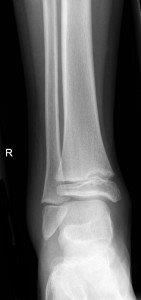

Avulsion fracture of distal fibula

Salter Harris I fracture of fibula

Undisplaced Salter Harris II fracture of fibula

Undisplaced epiphyseal fracture of distal fibula